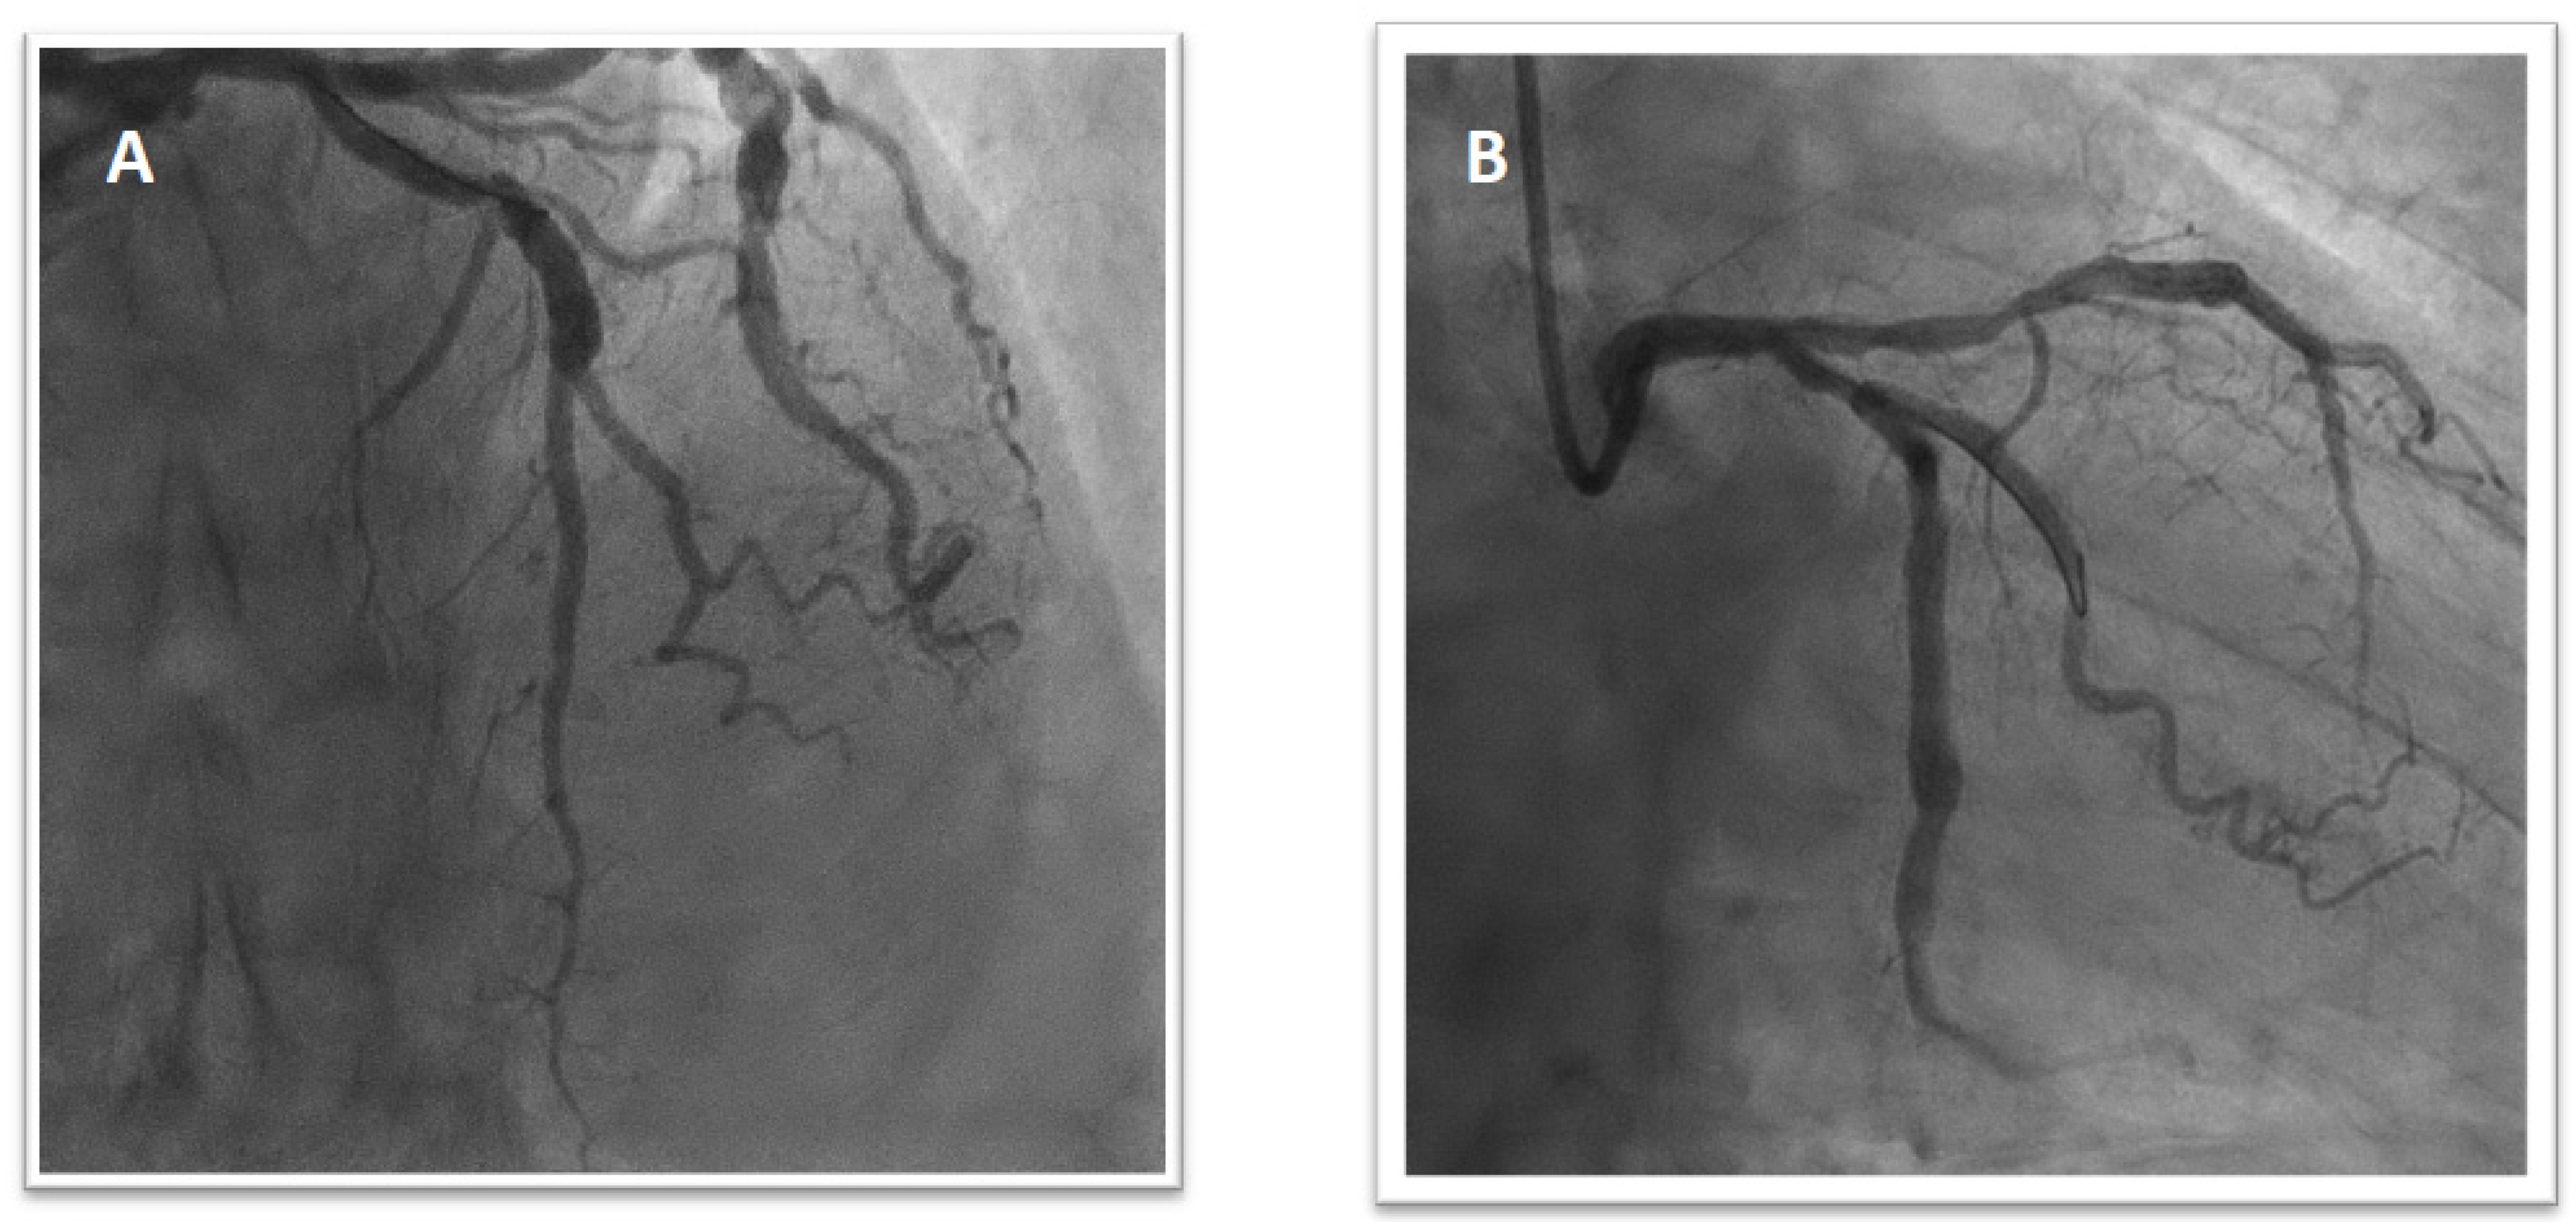

Figure 2.

Final result after the first intervention with the implantation of two polymer-free DES on the mid-LAD and second diagonal branch (T stent technique; 2.75 × 24 mm and 2.25 × 14 mm) (A). Final result after the second intervention with implantation of a DES in the proximal obtuse marginal artery (2.5 × 25 mm) (B).

Figure 3.

Angiogram showing critical stenosis of a large diagonal branch (A) treated with PCI and implantation of one DES (2.75 × 18 mm) (B).